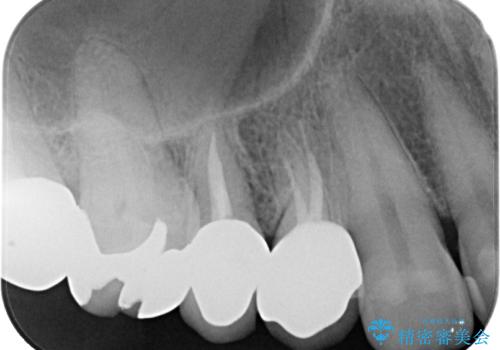

ファイバーコアを築造・精密な支台歯形成と印象採得

オールセラミッククラウンの装着